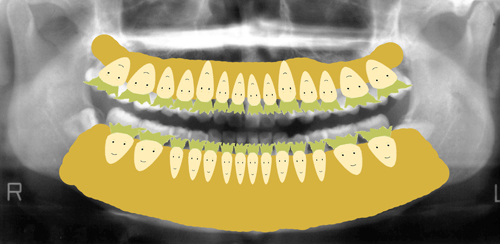

下の図でいえば

大根が歯、

黄土色部分が、骨です。

大根も顔の頭が見えているのは3分の1程度で

残りに3分の2は骨に埋まっています。